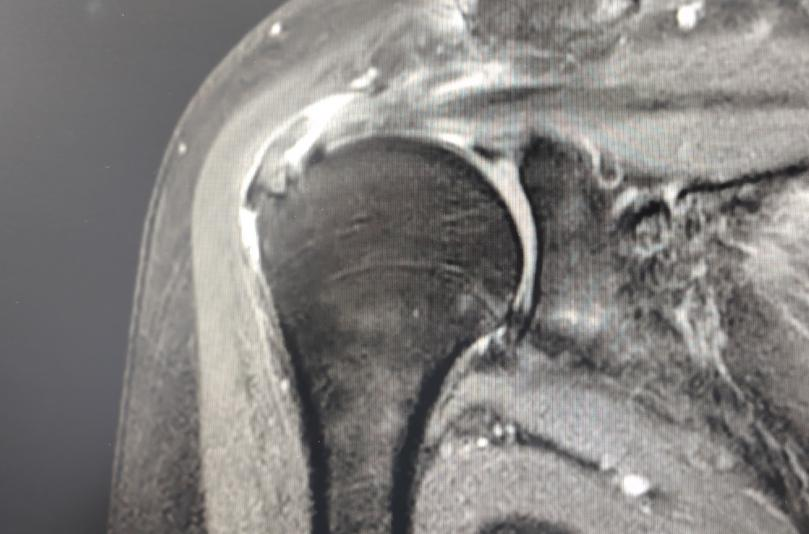

近期,一名八旬老妪因“右肩疼痛伴活动受限2月余”入住我院运动医学与关节外科,经检查后确诊“右侧肩袖损伤,并成功施行“关节镜下肩袖修补术”,术后恢复顺利,肩部疼痛缓解,功能显著改善,患者对治疗效果非常满意。

及时就医:医生通过检查(如磁共振 MRI)确诊损伤程度。